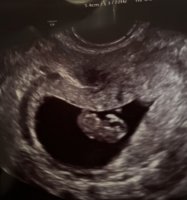

Gynekologen jeg var hos sist, 7+5, likte best å ha bildet opp ned, tydeligvis. Mulig det er det?

Et av bildene er iallfall vriddMen gynekolgen var var hos på 8+2 sa at livmorhalsen min lå til høyre for bildet (så egentlig tror jeg hele bildet er tatt fra siden på en eller annen måte.

Så denne teorien er jo ganske vanskelig om man ikke vet 100% hvilke vei på bildet som er riktig![]()

Jeg vet ikke helt om jeg forsto metoden.. Noen som vil hjelpe meg med å se på bildet? Det er tatt ca. 8+0, muligens litt for sent til å se det?![]()

Kort fortalt er det gjort en stor studie på 5000 tidlig ultralyder om at jentefoster fester seg på venstre side (morkake på venstre side) og omvendt for guttefoster (når man tar vaginal ultralyd.. om man tar utvendig ultralyd er sidene byttet om såklart) skal visst være 97 % sikkert. Prøv å Google det![]()